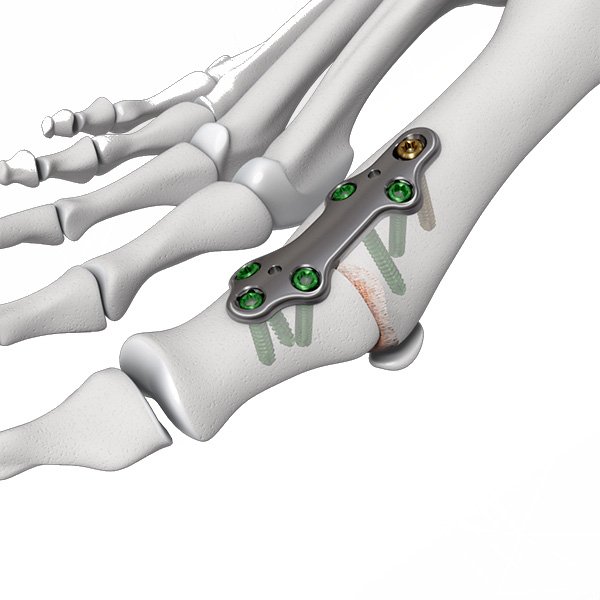

The First MTP Fusion Plate is an orthopedic implant specifically designed for stabilizing and fusing the first metatarsophalangeal (MTP) joint in cases of arthritis, deformities, or trauma. Made from high-quality Stainless Steel or Titanium, this plate provides strong, stable fixation to facilitate the fusion of the first MTP joint. The low-profile design minimizes soft tissue irritation, ensuring patient comfort during the healing process. Its precise screw placement allows for optimal alignment and fixation of the joint, promoting effective fusion and long-term joint stability.

- First MTP Joint Fusion : Ideal for stabilizing and fusing the first MTP joint in cases of arthritis, trauma, or deformities such as hallux rigidus.

- MTP Joint Fusion : Specifically designed to stabilize and support the fusion of the first MTP joint, aiding in effective bone healing.

- Anatomically Contoured : Designed to match the natural curvature of the first MTP joint for optimal fit and stability.